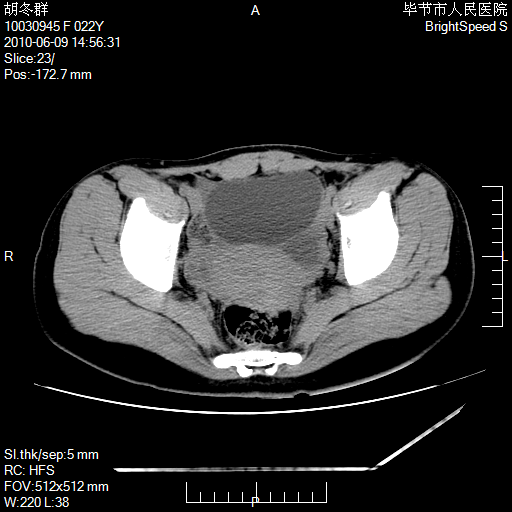

患者23岁,发现腹部包块3月。

盆腔内囊性占位;穿刺或者直接手术拿掉即可,不必紧张。

左侧卵巢囊腺瘤或囊腺癌

盆腔内囊性占位性病变;考虑左侧卵巢囊腺瘤。

有分隔、壁薄,支持考虑左侧卵巢囊腺瘤。

左侧卵巢浆液性囊腺瘤。

支持左侧附件区囊性占位,多考虑为囊腺瘤。

支持考虑左侧卵巢囊腺瘤;宫腔积液。

有分隔、壁薄,支持考虑左侧卵巢囊腺瘤。排尿后,膀胱缩小,由于重力作用,肿块下移就到了膀胱位置,很好理解。